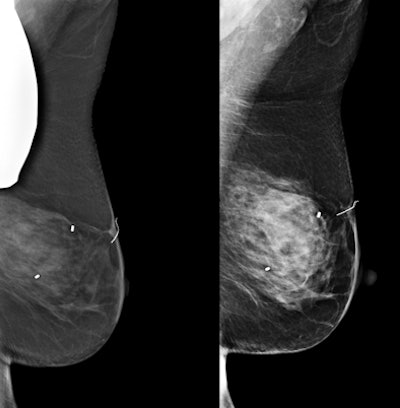

A technologist positioned for a mammogram with the thyroid shield in place. Part of the thyroid shield is underneath the compression paddle and would cause a portion of the breast to be obscured on the mammogram.

Rapelyea explained that a patient's body shape and mobility might prevent her from wearing a thyroid shield due to positioning requirements. She explained that in the past week, as patients at her center were demanding thyroid shields, approximately 20% of screening mammograms had to be repeated.